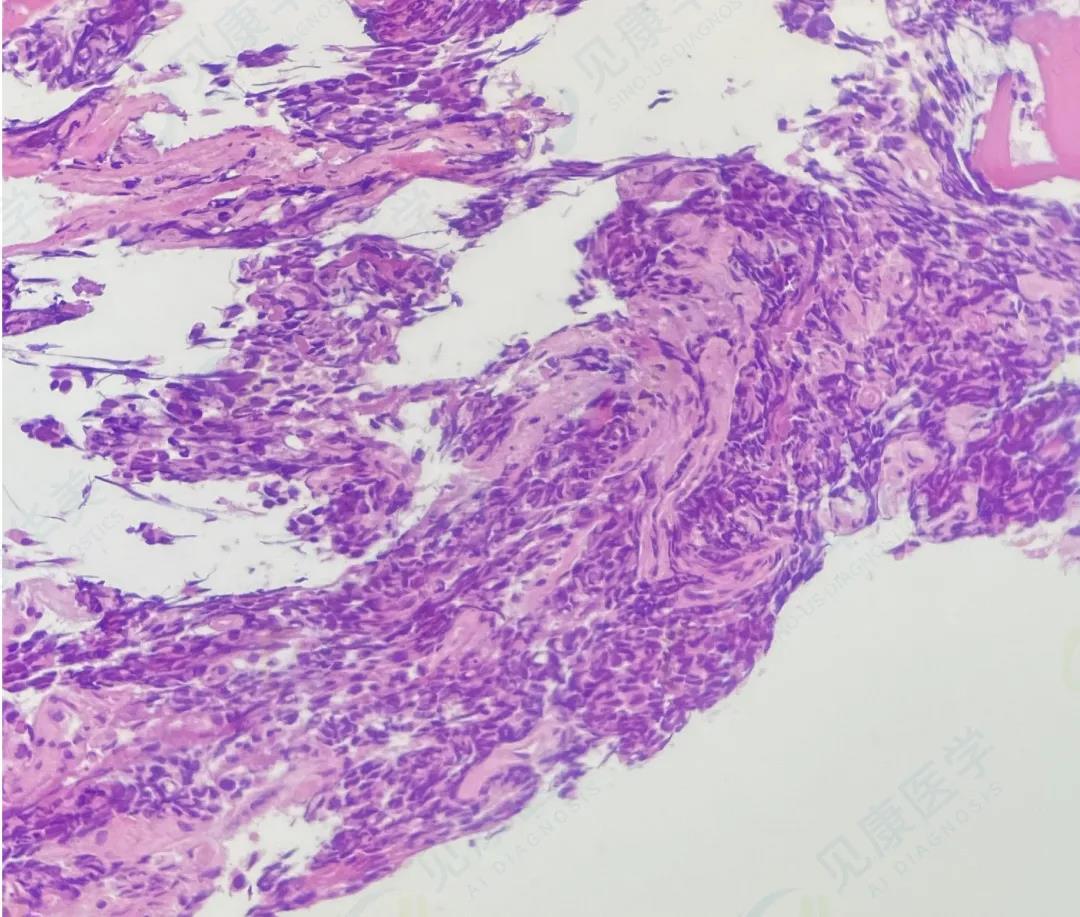

HE

骨髓转移癌

(临床后续检查为前列腺癌)